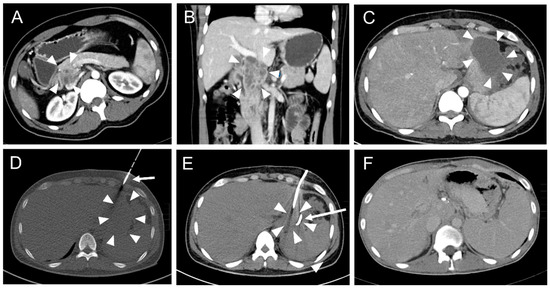

Primary placement of the drainage was successful in 165 interventions (Figure 2).

Figure 2. A typical CT fluoroscopy-guided drainage placement procedure after pancreatic surgery. (A) A 33-year-old male with a history of abdominal tuberculosis and the formation of an inflammatory pseudotumor in the pancreatic head (arrowheads). (B) Coronal reconstruction of the abdominal CT scan illustrates a multicystic mass of the pancreatic head (arrowheads) with close vascular relation to the portal vein and lower vena cava. (C) The patient developed subfebrile temperature and left epigastric pain 19 days after pylorus-preserving pancreaticoduodenectomy (PPPD). CT revealed a left paragastric serous fluid collection (arrowheads). (D) CT fluoroscopic image (10 mAs tube current). An 8F pigtail drainage was inserted into the fluid collection (arrowheads) with the trocar technique using an anterior intercosto-cartilaginary approach (arrow). (E) Post-interventional CT scan. Unenhanced post-drainage (arrow) CT scan showed significantly reduced paragastric fluid collection (arrowheads). Microbiological analysis of the aspirated fluid revealed infection with Serratia marcescens. (F) CT follow-up eleven months later showed complete resolution of the fluid collection. Note the increase of spleen size due to portal vein occlusion with beginning cavernous transformation.